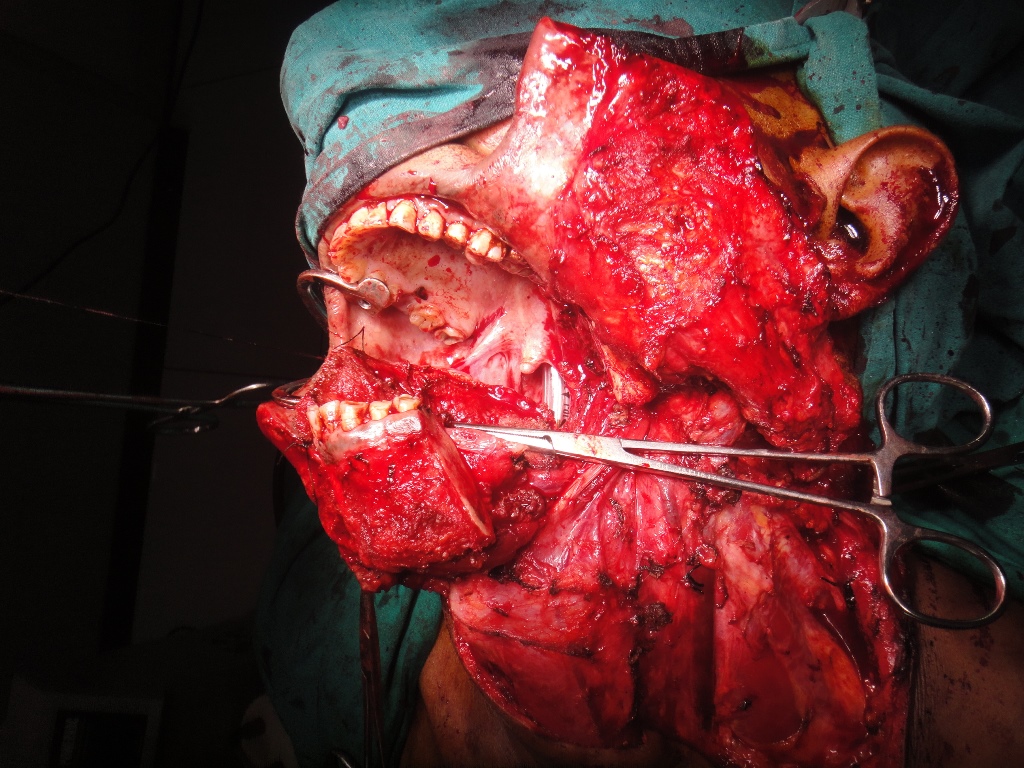

52 yrs old male suffering from right lower gingivo buccal carcinoma. Operated today for right radical neck dissection with right PM flap with right heminmandibulectomy.

31-12-2019